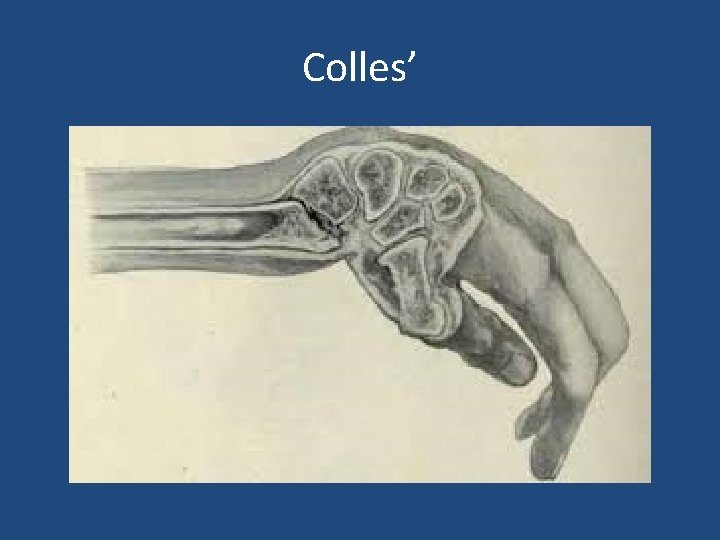

• Extra-articular: – Colles’ Fracture: dorsal angulation, shortening and radial deviation – Smith’s fracture: shortening and volar angulation. (reverse Colles’) • Intra-articular: – Barton’s fracture: volar or dorsal – others

Colles’